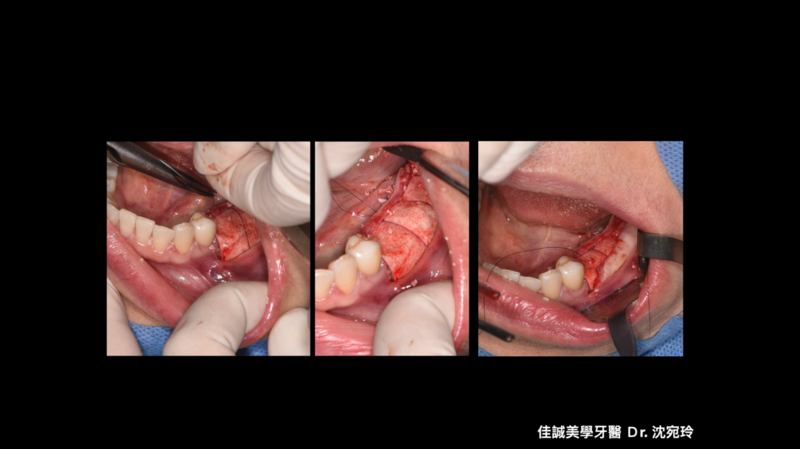

治療的開始是我們幫病患解決了疼痛,從病患腫痛,拆假牙、拔牙,恰好左下第一小臼齒為根管難症,仰賴錢正原醫師的成功顯微根管治療,取的病患的信任。接著我們一步步的重建,也因為這區是長達十幾年的五單位牙橋,拆掉後除了病患明顯左邊不好咀嚼,因此對於重建有強烈的企圖心,另外我們也看到因為長久缺牙而有牙脊萎縮,並伴隨角質化上皮缺損。缺損的骨頭部分我們是補得回來的,但一次三顆植體加上水平補骨,若在缺角質化上皮的這區手術,總覺得風險高了些。因為若有足夠的角質化上皮,可以讓我們植牙手術補骨縫合時,將縫線進針在角質化上皮內,縫線與角質化上皮內就像釘書針扎實的釘錨著,能對抗術後腫脹期防止傷口裂開,讓手術更能保證成功; 另外,若於其後補上骨粉和再生膜後,牙脊上的角質化上皮也相對穩定,不會在咀嚼時移動,讓其下方的骨粉可以好好轉換成自體骨; 角質化上皮的功能不只如上,在將來植體接假牙出來後,在咀嚼時,也因有足夠角質化上皮的包覆,能防止食物掉入和植體相接的牙肉內,防止植體周圍炎的產生。談到植體周圍炎的預防,植體植入的位置,最好平行假牙咬合軸向的受力,並且出孔位置在假牙的正中心。

以這個案例,我們量測了牙脊缺牙區的總寬度,再精算植體間距和植體寬度,後牙區小臼齒種植寬度長度4 mm X 11.5mm的植體,大臼齒則置入兩支寬度長度5 mmX11.5mm的植體,而在設計時在軟體內要讓三顆植體盡可能平行,以利將來植牙贋復製作,減少應力集中造成植體周圍炎的可能。我們利用模子的STL檔和斷層掃描的DICOM檔做疊合,在Bluesky軟體內,由醫師自己設計出最佳的植體位置、寬度長度,再請專業的3D列印公司做數位模板輸出。因為在軟體內我們已經看出將來植體的位置和需補骨的量,進而反推切線的位置,最後我們知道角質化上皮終究都需要補一場,於是治療計畫一開始就是先補上角質化上皮,等四個月後軟組織穩定,我們接著利用手術導板植入三個植體,並於當次補入骨粉和再生膜,術後如我們預期,傷口恢復良好。